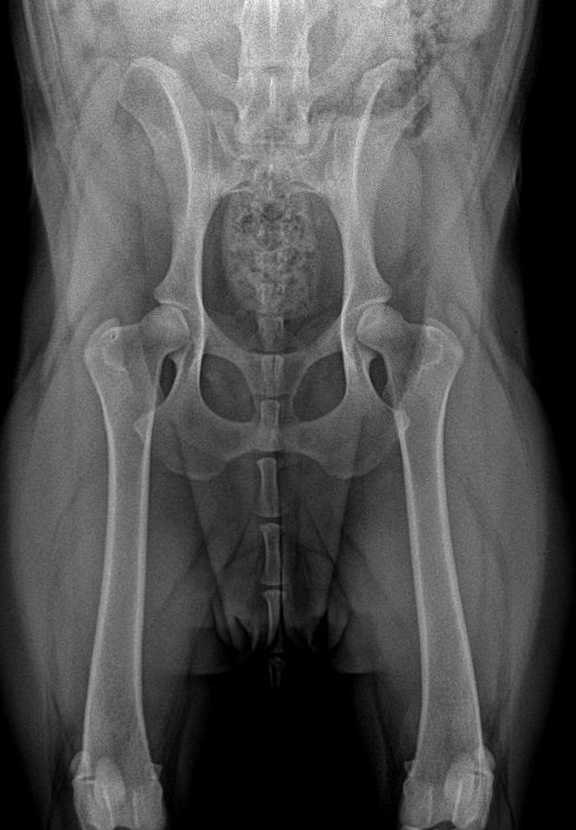

ДТБС у собак: рентгенограммы

ДТБС: степень "А" — норма